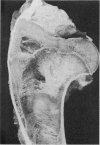

Nineteen lactating or recently weaned sows that had a history of lameness, weakness or paralysis were studied at necropsy. Ten sows had osteoporosis and pathological fractures while six had lumbar vertebral osteomyelitis. Values for bone ash, specific gravity of bone and the cortical to total ratio were significantly reduced in sows with osteoporosis and pathological fractures.